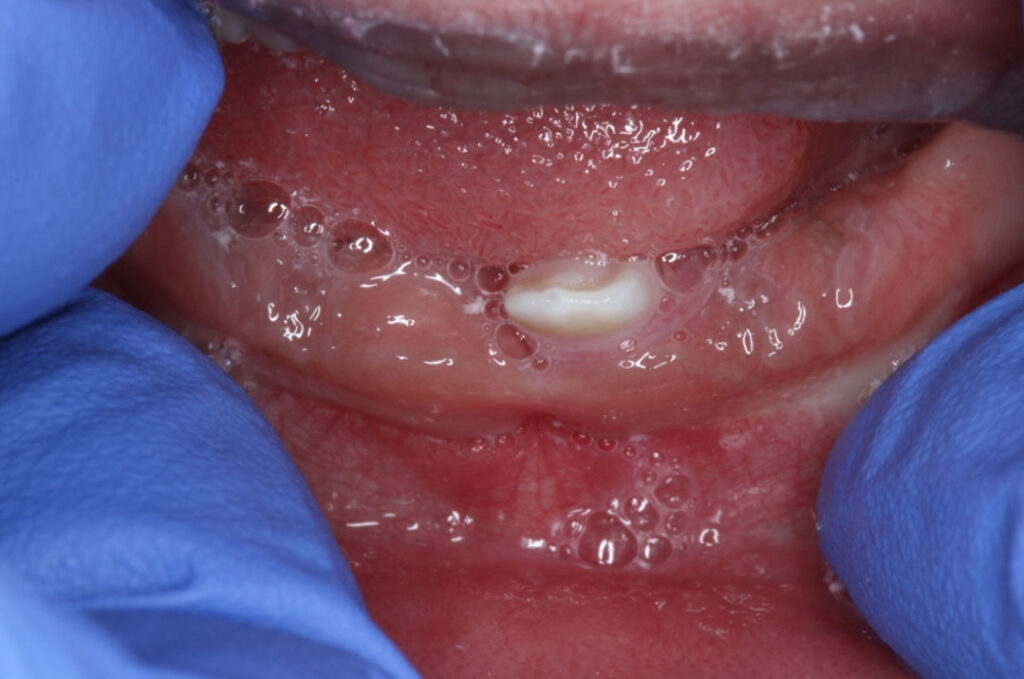

11-year-old boy with a large mass

An 11-year-old boy with a large mass over the right anterior maxilla.